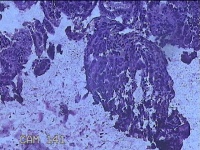

宫颈管内容物

性别

女

年龄

41岁

临床诊断

1.子宫内膜息肉 2.疤痕子宫

一般病史

阴道流血2天。

标本名称

大体所见

灰白暗红色不规则碎组织0.7x0.5x0.2cm一堆。